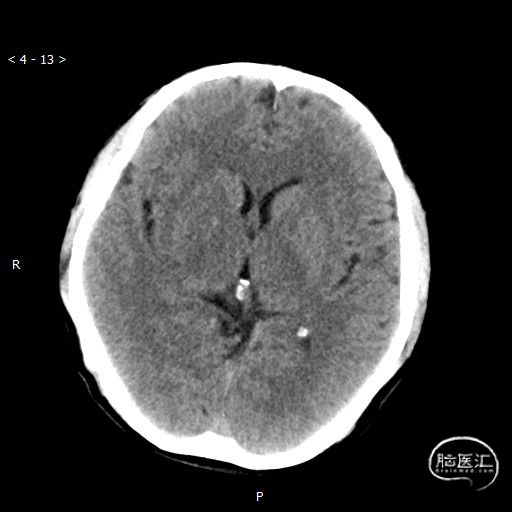

头颅CT(2020-05-04)

ASPECT 10分。

多模CT(2020-05-04)

术前评估: